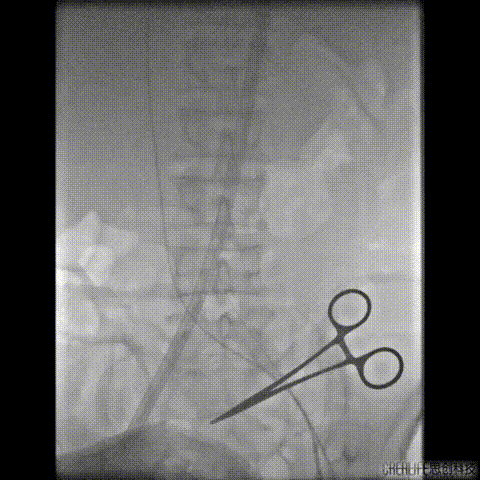

行急诊手术 腹主动脉及左侧股动脉造影

左侧股动脉见造影剂外渗

球囊压迫后植入覆膜支架

复查造影